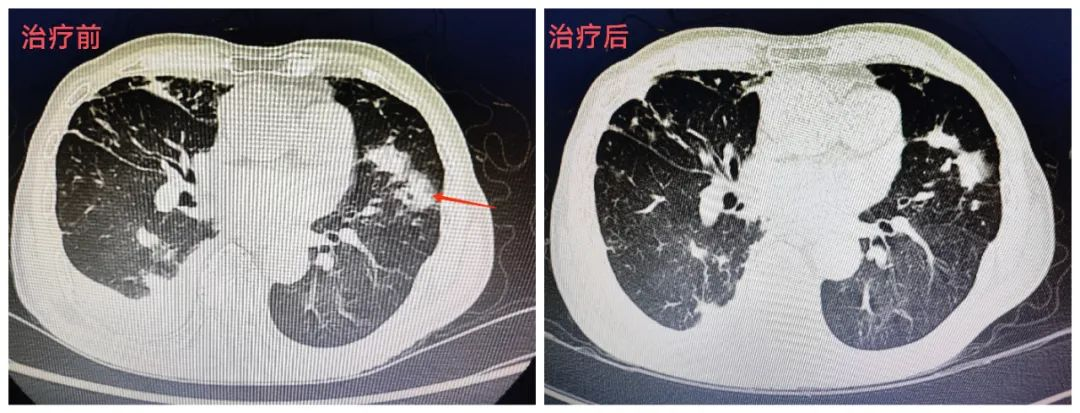

最后,医师团队予加用阿米卡星、克拉霉素、利福平、乙胺丁醇;治疗3天后,患者体温终于恢复正常。经过对病情抽丝剥茧,细致分析,即予以规范治疗,患者病情逐渐好转,复查胸片、胸部CT病灶吸收,目前仍在巩固治疗阶段。

▲8月25日胸部CT

▲9月5日复查胸部CT